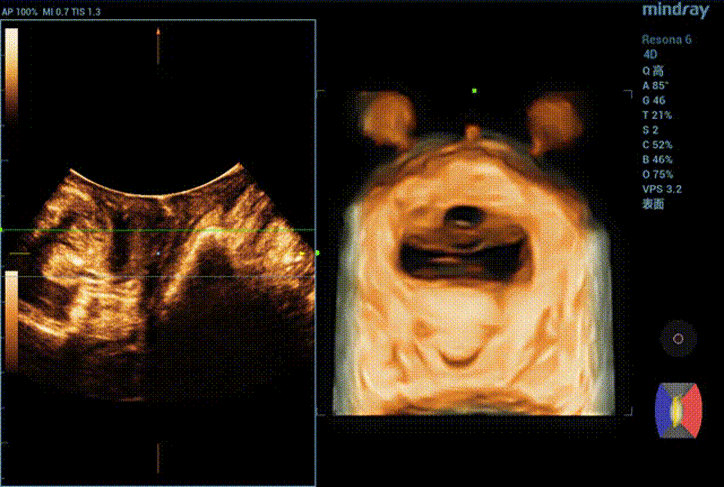

During maximal Valsalva maneuver, the bladder neck is 14mm below the pubic symphysis , the lowest point of bladder is 16.9mm below, the uterus is 7.3mm above and the rectum is 10.4mm below. The levator ani hiatus is 26.06cm2 (see Figure 2).

Figure 3 Two-dimensional ultrasound show the movement of pelvic floor during Valsalva